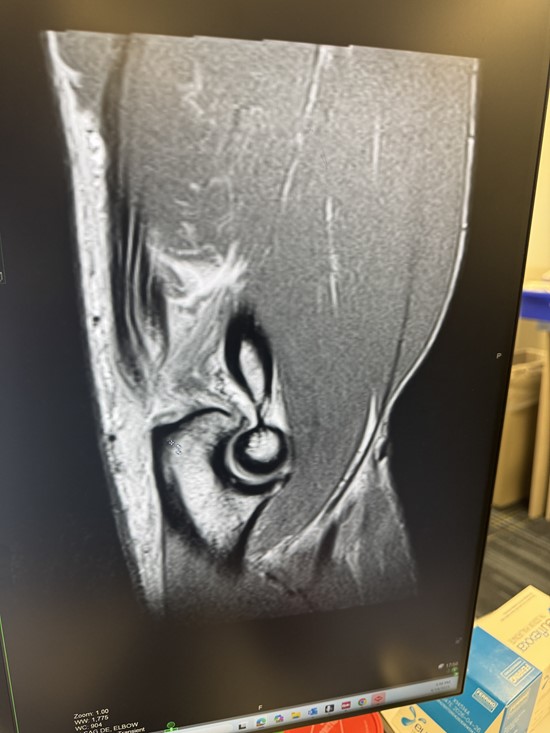

Jeff Sciullo WWE/TNA professional wrestler torn tricep

To view an enhanced version of this graphic, please visit:

https://images.newsfilecorp.com/files/10520/281838_img_0603.jpeg